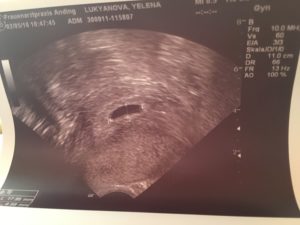

Первое УЗИ после удачного ЭКО назначают на 21–28 день после переноса (ДПП) плодного яйца. Но этот период зависит от клиники: некоторые врачи отправляют пациентку на ультразвуковое исследование только на 6 неделе после положительных результатов анализов. В этот период можно даже услышать сердцебиение плода, а сам эмбрион отлично просматривается на экране монитора.

- На 21 день после переноса эмбрионов врач уже может увидеть плодное яйцо, диагностировать благополучную беременность.

Первое УЗИ после ЭКО назначают на 21 – 28 сутки после экстракорпорального оплодотворения. Это стандартная процедура диагностики, позволяющая обнаружить не только беременность, но и положение ребенка, состояние организма будущей матери.

Таким образом, первое ультразвуковое исследование делается позже – на 21 день. Среди врачей нет определенной точки зрения на оптимальный срок проведения первого УЗИ.

Начиная с 20 дня после эмбриональной подсадки врачом проводится УЗИ, которое дает возможность рассмотреть плодное яйцо полностью.